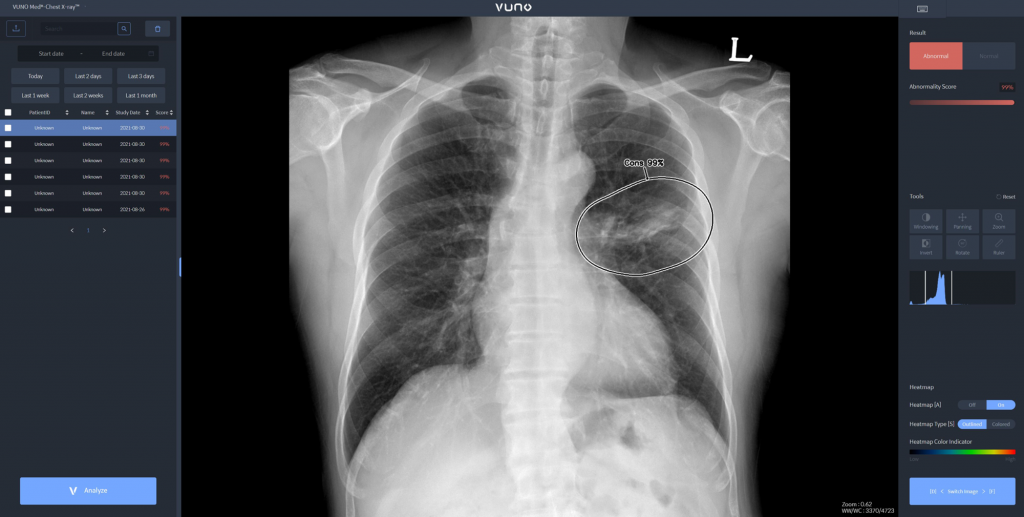

“VUNO Med Chest X-ray™” is an AI solution that accurately detects major anomalies such as nodules, calcifications, pleural effusion, and pneumothorax in chest X-ray images. It aids medical professionals by identifying and locating abnormal findings, thus facilitating the diagnosis of critical lung diseases, including tuberculosis and pneumonia. A notable feature of this solution is its lightweight model, which ensures easy integration with a wide range of X-ray equipment.